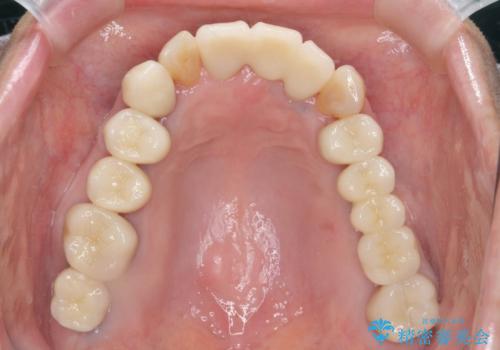

期間は約2年ほどかかりましたが、審美的な仕上がりとともに清掃のしやすさも非常に満足いただくことができました。